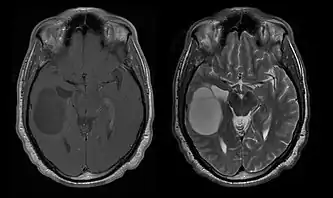

La tomodensitométrie (TDM) et L'imagerie par résonance magnétique (IRM) peuvent détecter efficacement une néoplasie dans le cerveau. L'IRM est plus sensible que la TDM pour identifier les lésions, mais présente des contre- indications pour les patients porteurs de stimulateurs cardiaques, de prothèses incompatibles, de clips métalliques et contre-indications. La TDM reste la méthode de choix pour détecter les calcifications au sein des lésions ou les érosions osseuses de la calotte ou de base du crâne. L'utilisation d' agents de contraste, iodés dans le cas du scanner et paramagnétiques (gadolinium) dans le cas de l'IRM, permet l'acquisition d'informations sur la vascularisation et l'intégrité de la barrière hémato-encéphalique, une meilleure définition de la tumeur tumorale par rapport à l' œdème environnant et à la génération d' hypothèses sur le degré de malignité. L'examen radiologique permet également d'évaluer les effets mécaniques et les modifications importantes des structures cérébrales résultant de la tumeur, telles que l' hydrocéphalie et les hernies, dont les effets peuvent être fatals. Enfin, en préparation à la chirurgie, ce diagnostic peut être utilisé pour déterminer la localisation de la lésion ou l'infiltration de la tumeur dans des zones vitales du cerveau. À cette fin, l'IRM est plus efficace que la tomodensitométrie car elle peut fournir des images en trois dimensions.

Les outils d'imagerie radiologique diagnostique mettent en évidence la modification du tissu néoplasique par rapport au parenchyme cérébral normal (par le biais de modifications de la densité tissulaire imagée électroniquement en TDM et de l'intensité du signal en IRM). Comme la plupart des tissus pathologiques, les tumeurs sont également reconnaissables par une accumulation accrue d'eau intracellulaire. Dans la tomodensitométrie, ils apparaissent hypodenses, c'est-à-dire de moindre densité que le parenchyme cérébral, dans la tomographie par résonance magnétique nucléaire avec relaxation spin-réseau hypointense et en relaxation spin-spin ainsi que l' hypersignal en pondération protonique (PD).

La tomodensitométrie du cerveau montre généralement une masse tissulaire qui peut être améliorée par l'un ou l'autre contraste. Au scanner, les gliomes de bas grade apparaissent généralement isodenses au parenchyme normal et peuvent donc ne pas présenter de rehaussement de contraste. De même, les lésions de la fosse crânienne postérieure sont difficiles à identifier au scanner. Par conséquent, les seuls résultats d'une telle tomographie ne sont pas toujours suffisants à des fins diagnostiques. Dans les cas douteux, l'utilisation de l'imagerie par résonance magnétique plus sensible est indispensable.

Sur-L'IRM montre une tumeur intracrânienne comme une lésion massive qui peut devenir plus luminescente après utilisation du produit de contraste. Cependant, il y a toujours une anomalie de signal dans -L'imagerie par résonance magnétique, qui indique la présence d'une néoplasie ou d'un œdème vasogénique. Habituellement, une luminescence accrue (amélioration du contraste) indique une tumeur d'un grade supérieur de malignité. Un anneau de contraste est caractéristique du glioblastome, avec la partie luminescente correspondant à la partie vitale de la tumeur maligne, et la plus foncée - zone hypointense correspondant à une nécrose tissulaire.